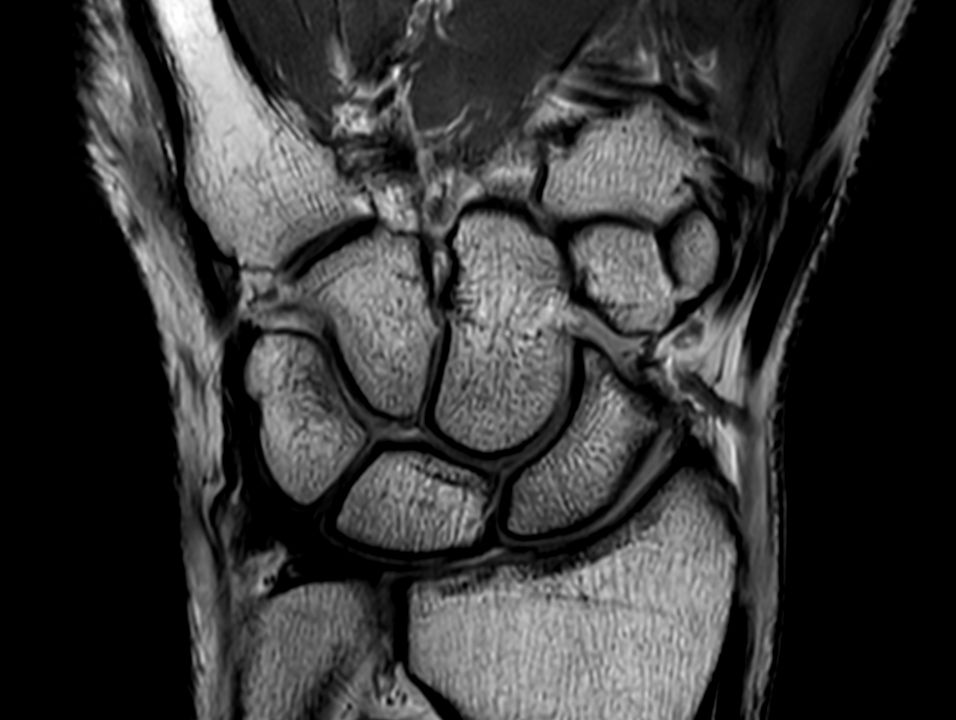

Coronal PDw TSE

Coronal PDw TSESmartSpeed

Coronal PDw TSESmartSpeed High Resolution